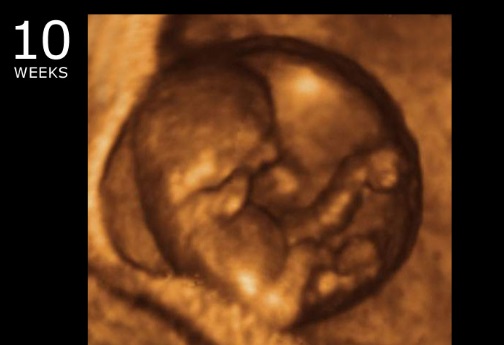

10 Weeks Pregnant Week By Week Obstetrics And Gynecology Ob